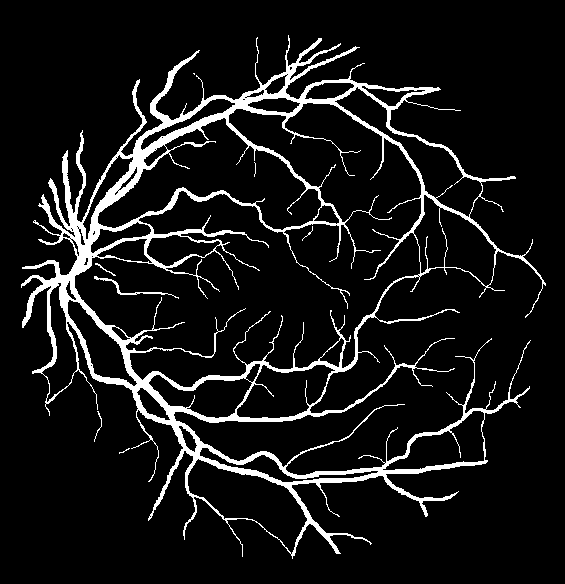

The evaluation of each experiment over the five different initialization roll-outs are reported in Table 1-4. The mean and standard deviations of five commonly used metrics, namely specificity, sensitivity, F1 score, accuracy and the AUC score are presented. The threshold for binarization is selected such that the F1 score is maximized on the validation sets. The threshold independent AUC score is chosen as the main performance indicator. The output probability maps of the degenerated trials are presented in Fig. 2 (c-f).